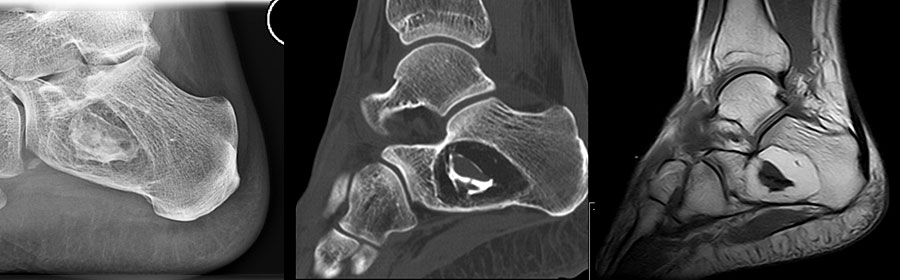

Sobald eine osteolytische Knochenläsion des Calcaneus erscheint, ist eine weiterführende Abklärung mittels MRT indiziert. Das intraossäre Lipom des Calcaneus lässt sich im Röntgen nur dann von der simplen Knochenzyste unterscheiden, wenn zentrale, dystrophe Verkal­kungen vorliegen (Abb. 25). Diese auch als Nidus oder Sequestrum bezeichneten Kalzifi­kationen sind typisch, jedoch nicht obligat für das intraossäre Lipom.

Die juvenile Knochenzyste (Syn. Solitäre Knochenzyste) findet sich am Fuß fast ausschließlich am Calcaneus im Bereich des Ward´schen Dreieckes bzw. im ventralen triangulären Bereich zwischen den Haupttrabekelgruppen (Diard´s Area 6) 3536. Eine physiologische Rarefi­zierung der Trabekelstrukturen in diesem Bereich muss strikt von tumorösen Raumforde­rungen differenziert werden 3738. Die Hauptindikation einer operativen Therapie stellen Schmerzen und eine drohende pathologische Fraktur dar (Abb. 23). Calcaneuszysten, die in der Koronarebene 100% des Querschnitts erreichen oder 30% der Sagittalebene einneh­men, gelten als potentiell frakturgefährdet und sollten auch bei Symptomfreiheit prophylak­tisch operiert werden 3940 (Abb. 24). Da simple Knochenzysten nicht selten als radiolo­gischer Zufallsbefund auffallen, kann auch die Tumorangst des Patienten eine Indikation darstellen. Eine differenzierte Aufklärung des betroffenen Patienten (und seiner Eltern) ist hier umso mehr erforderlich.